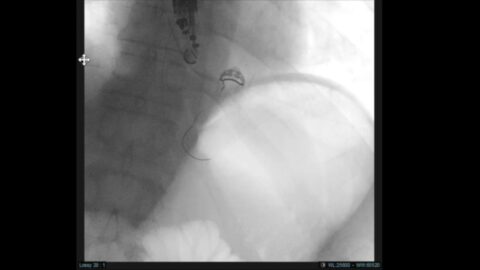

Reperméabilisation gastro-gastrique pour CPRE chez une patiente avec un by-pass